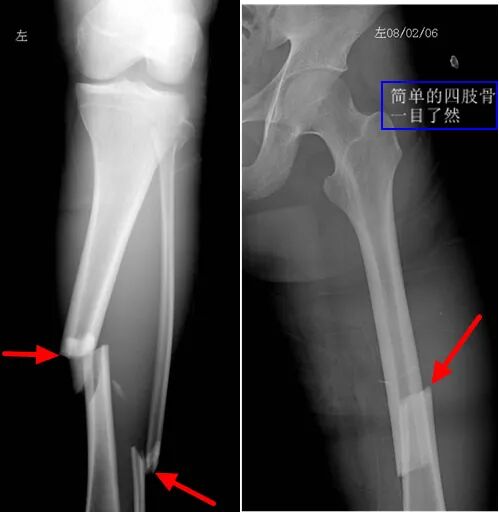

如果四肢、脊柱等部位受到急性创伤,伴有突发急性疼痛或受伤后的慢性疼痛,一般会优先选择DR。

观察四肢骨折比较直观(如下图分别为左胫腓骨骨折,左股骨骨折,用红箭头标明骨折处)